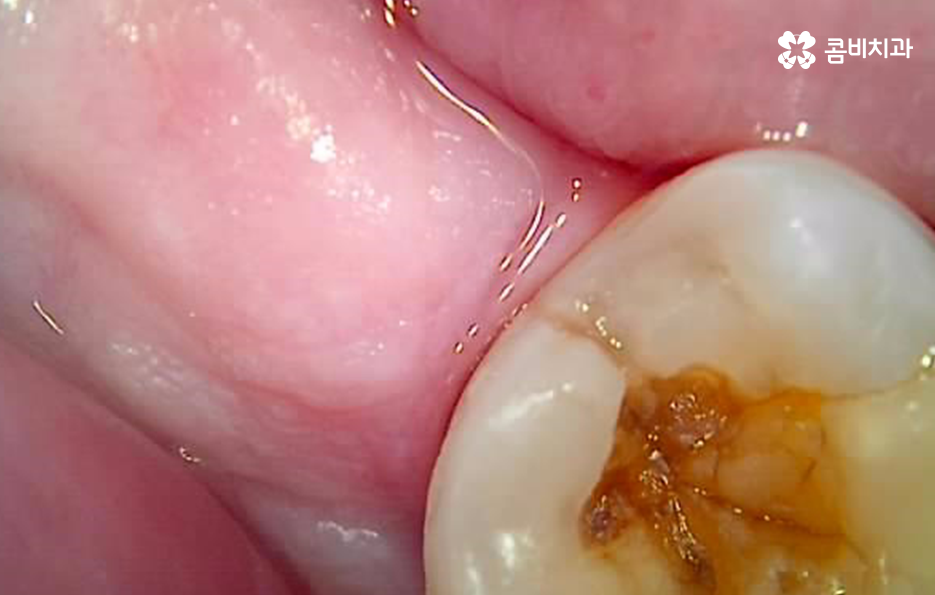

치아와 치아 사이가 맞닿는 부분은 평소 치실이나 치간칫솔을 사용하지 않는다면 칫솔질 만으로는 잘 닦이기 않기 때문에 충치가 자주 발생되는 부위는 아니지만 한번 발생되면 치아 양쪽으로 발생하기도 쉽고 치아 뿌리 쪽이나 신경 쪽에 가깝게 발생되는 경우도 많아서 간단히 레진으로 치료가 어려운 경우가 많고 보통 인레이나 크라운 치료로 이어지는 경우가 많이 있어요

물론 환자분들에 따라 구강 상태는 다르기 때문에 1:1로 정확히 검진해야 하는 것이 원칙이지만 치아 사이 충치의 경우 단순히 좀더 지켜보자는 관점으로 별다른 대처 없이 치료만 미루기에는 리스크가 클 수 밖에 없고 정확한 원인 치료와 개선을 함께 하면서 현재 문제가 되고 있는 충치를 늦지 않게 치료하는 것이 중요할 거예요

치아 사이에 발생되는 충치는 평소 주기적인 검진과 스케일링을 통해 예방하는 것이 최우선이겠지만 이미 충치가 발생되었다면 자연치아의 손상을 되도록 줄이는 치료를 하고 재발 방지를 위해서도 원인 치료를 제때 하시길 권하고 있어요